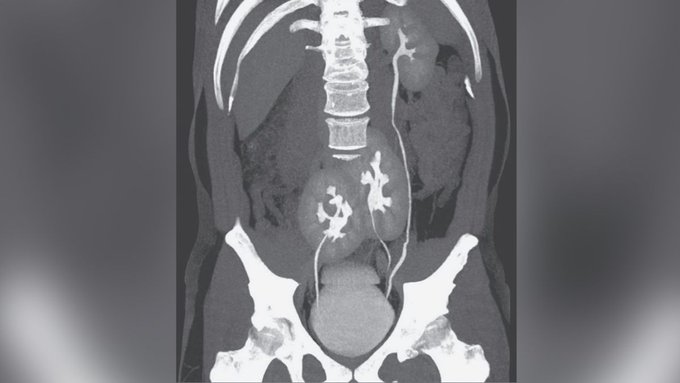

ولمعرفة سبب الألم الشديد للرجل البالغ من العمر 38 عاما، أجرى الأطباء في مستشفى "دو ريم" في ساو باولو بالبرازيل، فحصا بالأشعة المقطعية لتقييم المنطقة، وفقا لتقرير الحالة الذي نشر يوم الأربعاء 6 مايو، في مجلة نيو إنغلاند الطبية The New England Journal of Medicine.

وقال التقرير إنه بدلا من الكليتين المعتادتين اللتين يتم رؤيتهما لدى كل شخص طبيعي، كان لدى الرجل ثلاث كلى: كلية ذات مظهر طبيعي على جانبه الأيسر وكليتين منصهرتين تقعان بالقرب من الحوض.

ومن النادر وجود ثلاث كلى، حيث تم الإبلاغ عن أقل من 100 حالة في الأدبيات الطبية، وفقا لتقرير 2013 لحالة مماثلة نُشرت في The Internet Journal of Radiology. ويُعتقد أن الحالة تنشأ أثناء التطور الجنيني، عندما تنقسم بنية تشكل عادة كلية واحدة إلى قسمين.ولم يكن لدى الرجل أي أعراض لمشكلة في الكلى، وبدا أن الأعضاء تعمل بشكل طبيعي.